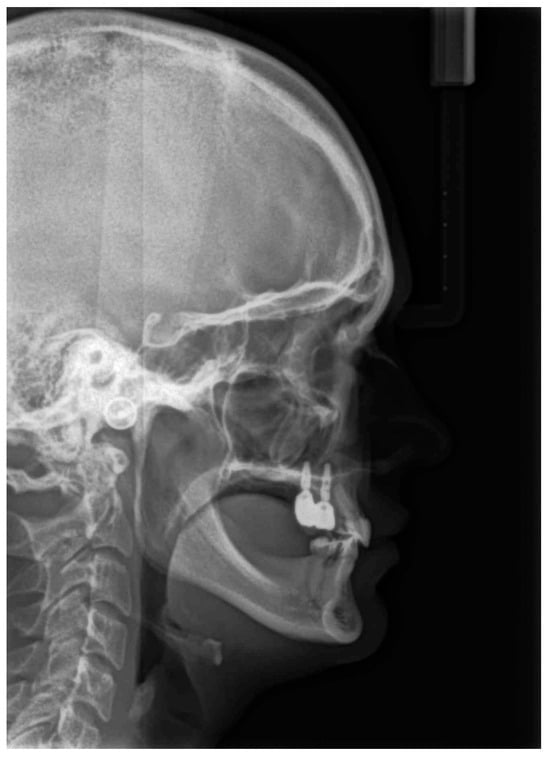

| Measurement | Norm | Deviation | Value |

|---|---|---|---|

| SNA | 82.0° | ± 3.0 | 82.9° |

| SNB | 80.0° | ± 3.0 | 83.6° |

| ANB | 2.0° | ± 2.0 | −0.7° |

| SNPg | 81.0° | ± 3.0 | 86.0° |

| GntgoAR | 122.0° | ± 7.0 | 121.8° |

| NL-NSL | 8.0° | ± 4.0 | 3.1° |

| ML-NSL | 28.0° | ± 5.0 | 26.2° |

| ML-NL | 20.0° | ± 7.0 | 23.1° |

| 1+:NA | 21.0° | ± 4.0 | 17.2° |

| 1+:NA (mm) | 3.7 mm | ± 2.0 | 3.2 mm |

| 1+:NL | 110° | ± 6.0 | 104° |

| 1−:NB | 24.0° | ± 4.0 | 10.5° |

| 1−:NB (mm) | 3.8 mm | ± 2.0 | 0.4 mm |

| 1−:ML | 94° | ± 7.0 | 79.2° |

| 1−:APg | 1.0 mm | ± 2.0 | −1.4 mm |

| 1+:1− | 133.0° | ± 8.0 | 153.5° |

| UL—“E” plane | −4.7 mm | ± 2.0 | −4.35 mm |

| LL—“E” plane | −2.0 mm | ± 2.0 | −4.45 mm |